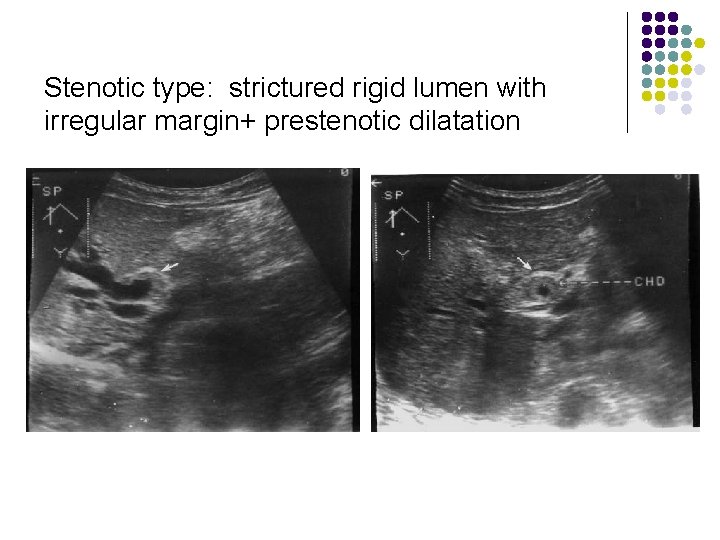

Cholangiocarcinoma: extrahepatic cholangiocarcinoma= bile duct carcinnoma Growth pattern: l Obstructive type : U/V-shaped obstruction with nipple , rattail, smooth/ irregular termination l Stenotic type: strictured rigid lumen with irregular margin+ prestenotic dilatation l Polypoid/ papillary type : intraluminal filling defect with irregular margins

Stenotic type: strictured rigid lumen with irregular margin+ prestenotic dilatation